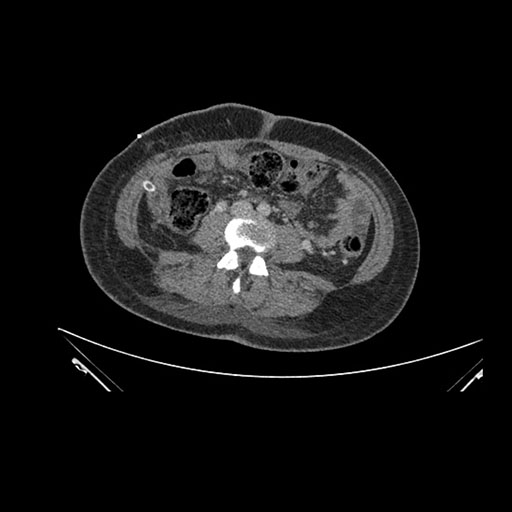

Imaging Analysis

Look through the patient's CT scan to identify any areas of concern for the necessary procedure.

Axial Venous

Based on initial findings, which issue(s) would you be most concerned about?